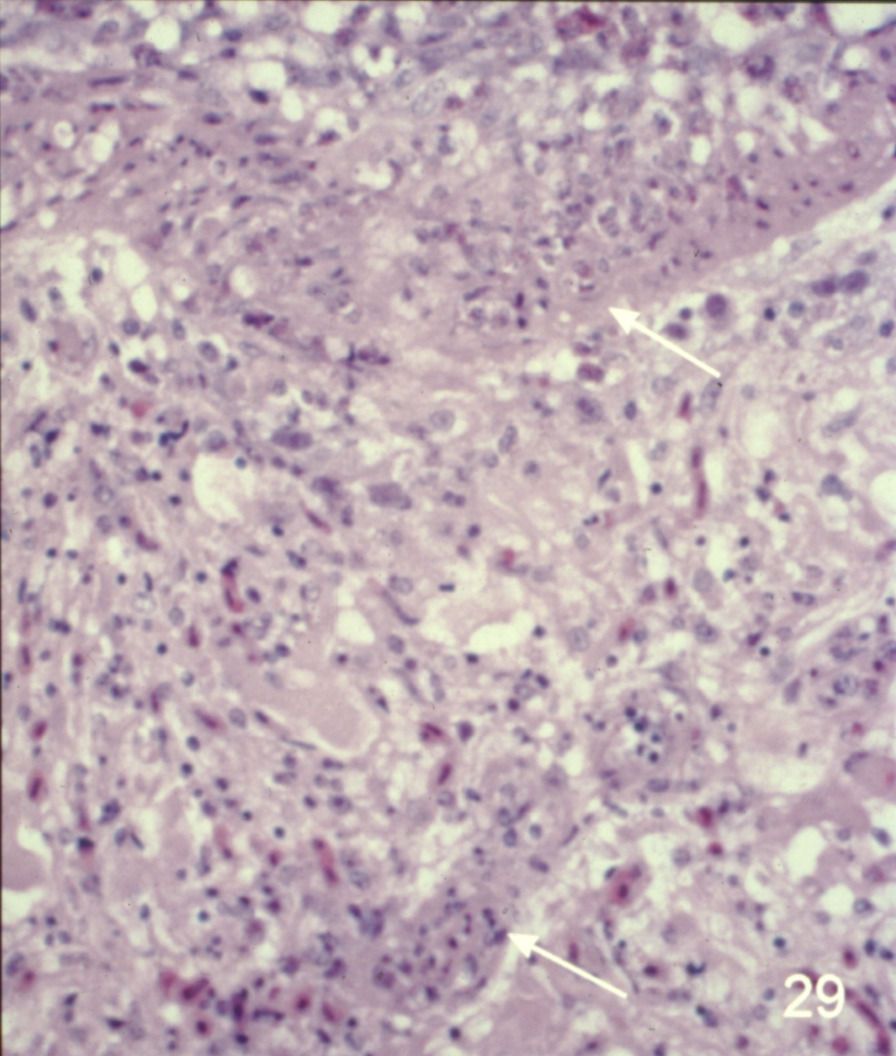

Cardiovascular disease in turkeys (slide study set no. 24) Item Info

Cardiovascular disease in turkeys (slide study set no. 24)

Turkeys--Diseases Cardiovascular system--Diseases

Slide Study Set #24, Cardiovascular Diseases in Turkeys (includes 27 color slides), 2001